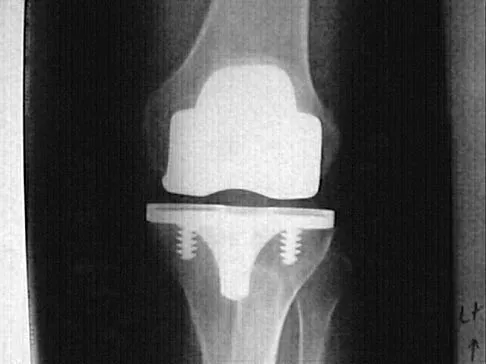

Osteolysis after total knee arthroplasty can be minimized through prosthetic design features such as

A 52-year-old woman has bicompartmental osteoarthritis following patellectomy. Treatment should consist of